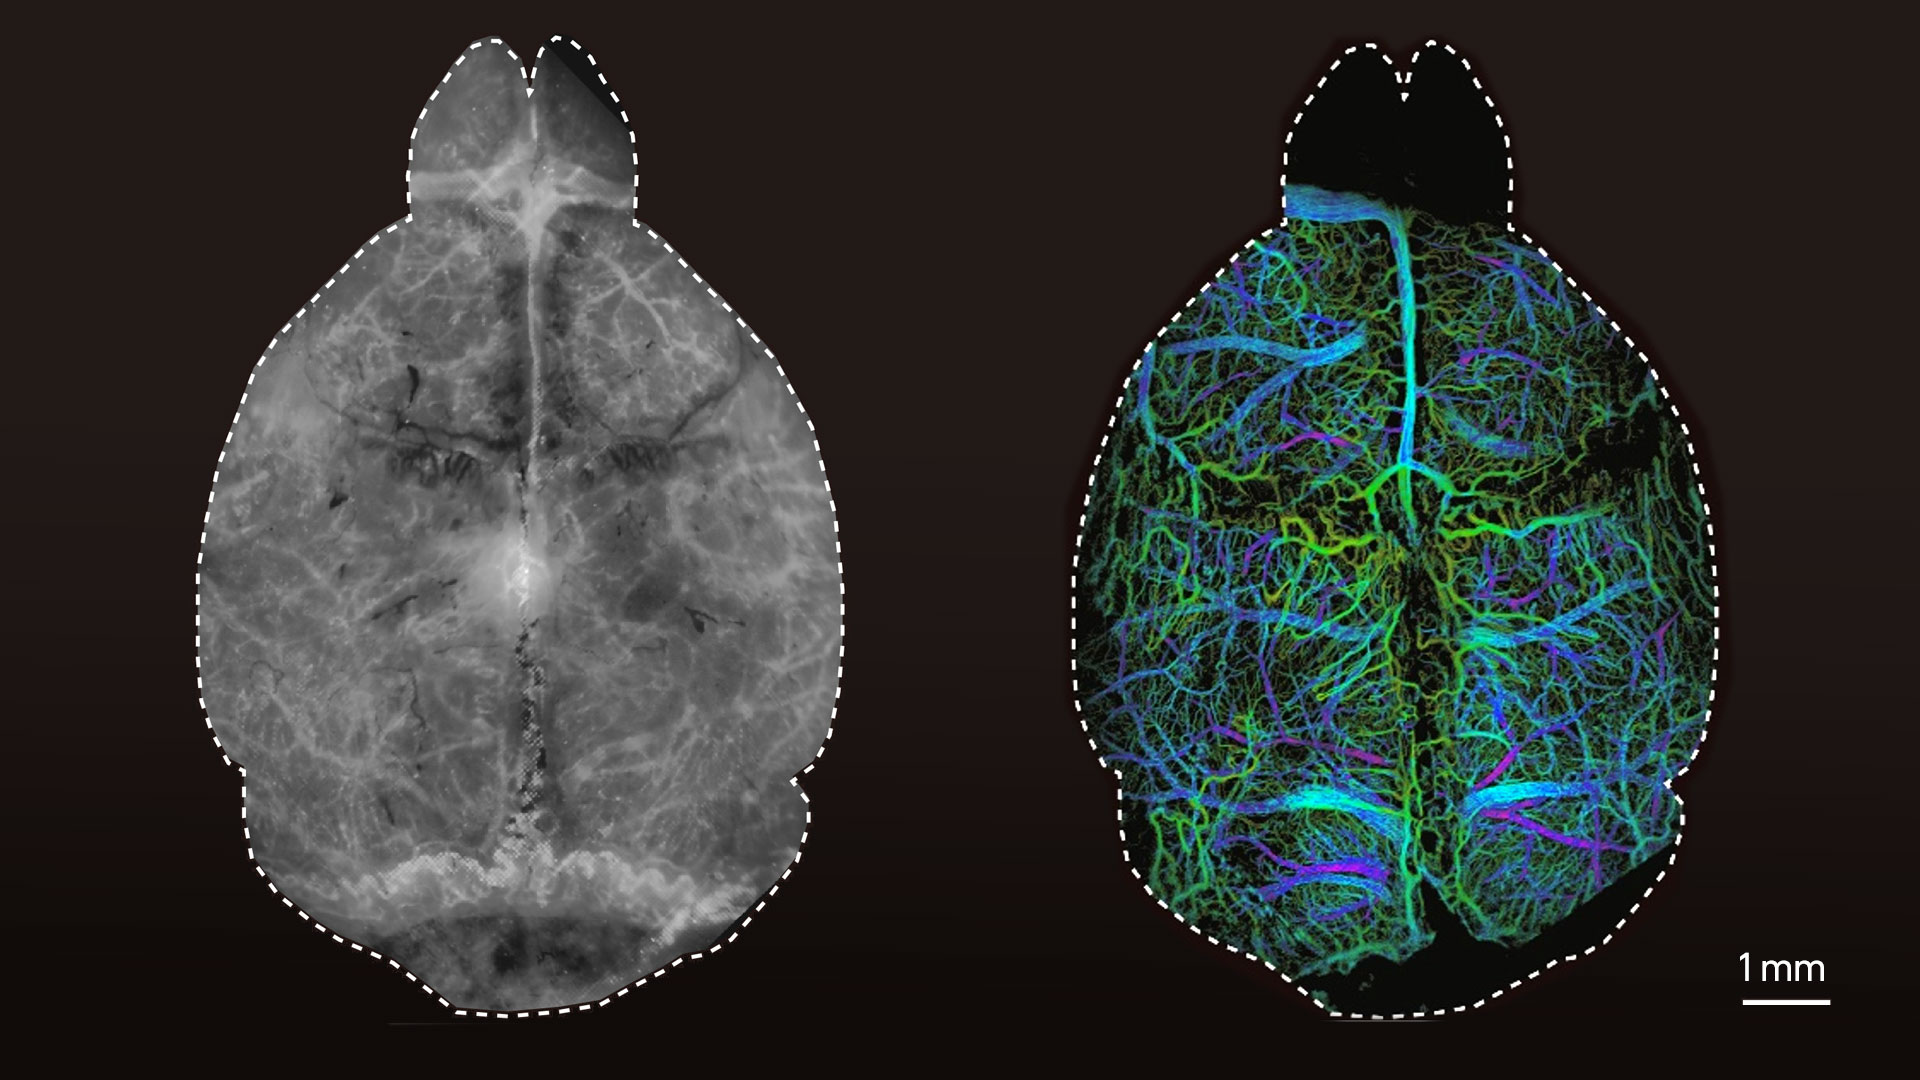

Die Forschenden testeten die neue Technik zunächst anhand von synthetischen Gewebemodellen, welche die Eigenschaften von Gehirngewebe simulieren. Das Resultat: Die Eindringtiefe der Bilder war vier Mal so hoch wie bei konventionellen fluoreszenzmikroskopischen Ansätzen. Anschliessend injizierten Razansky und sein Team lebenden Mäusen Mikrotröpfchen, welche fluoreszierende Quantenpunkte enthielten. Diese Tröpfchen konnten dann einzeln unter dem Mikroskop lokalisiert werden.

«Wir waren damit erstmals in der Lage, die kleinsten Gefässstrukturen und die Durchblutung tief im Gehirn der Maus scharf und nichtinvasiv sichtbar zu machen», sagt Razansky. Zudem beobachteten die Forschenden der ETH und der Universität Zürich, dass die Grösse der abgebildeten Mikrotröpfchen davon abhängig ist, wie tief sie sich im Gehirn befinden. Dieser Effekt erzeugt die dreidimensionalen Bilder der DOLI-Technik.